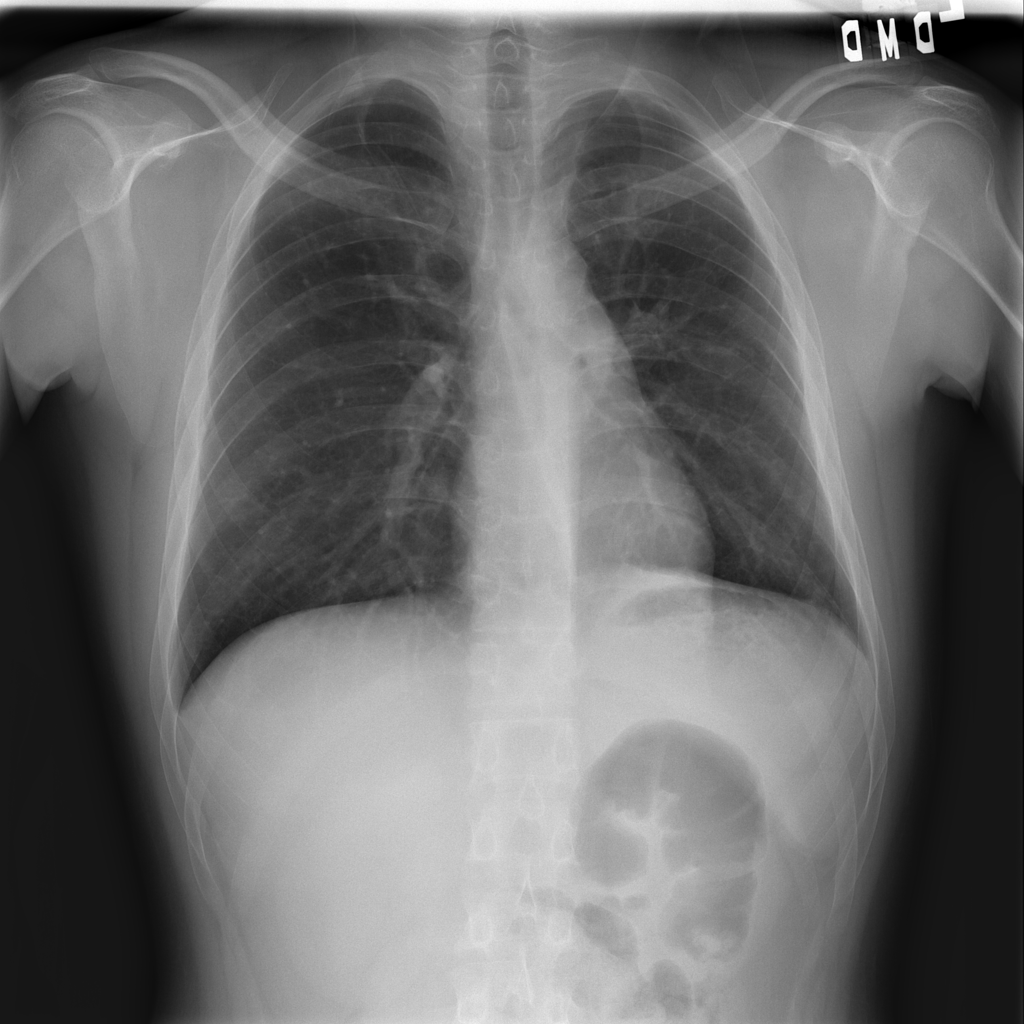

PAT-B733 · IMG-000Consolidation

PAT-B733 · IMG-000

PA